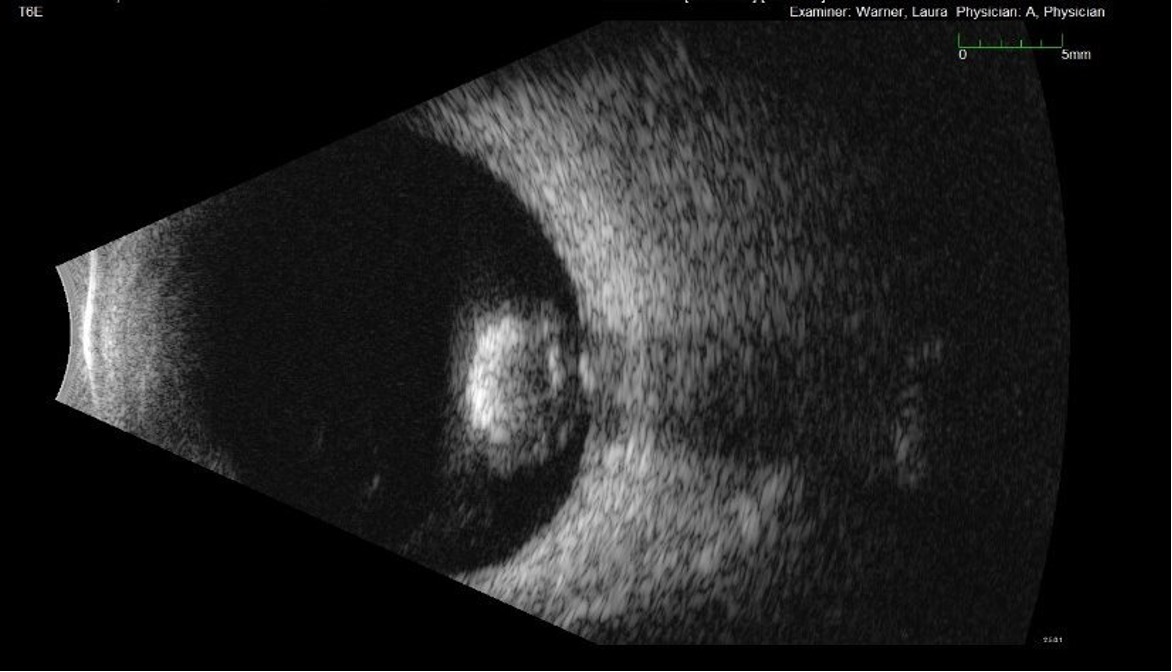

• B-scan ocular ultrasound was obtained in the left eye on initial presentation; findings are presented in Figures 2a, 2b (photos) and Figure 3 (video).

Figure 2a,2b. This is a formal B-scan oriented at L3 (2a, top) and T6E (2b, bottom), which shows the dense cataractous dislocated lens has fallen to the back and is resting on the retina. Notice the completely intact lens capsule.